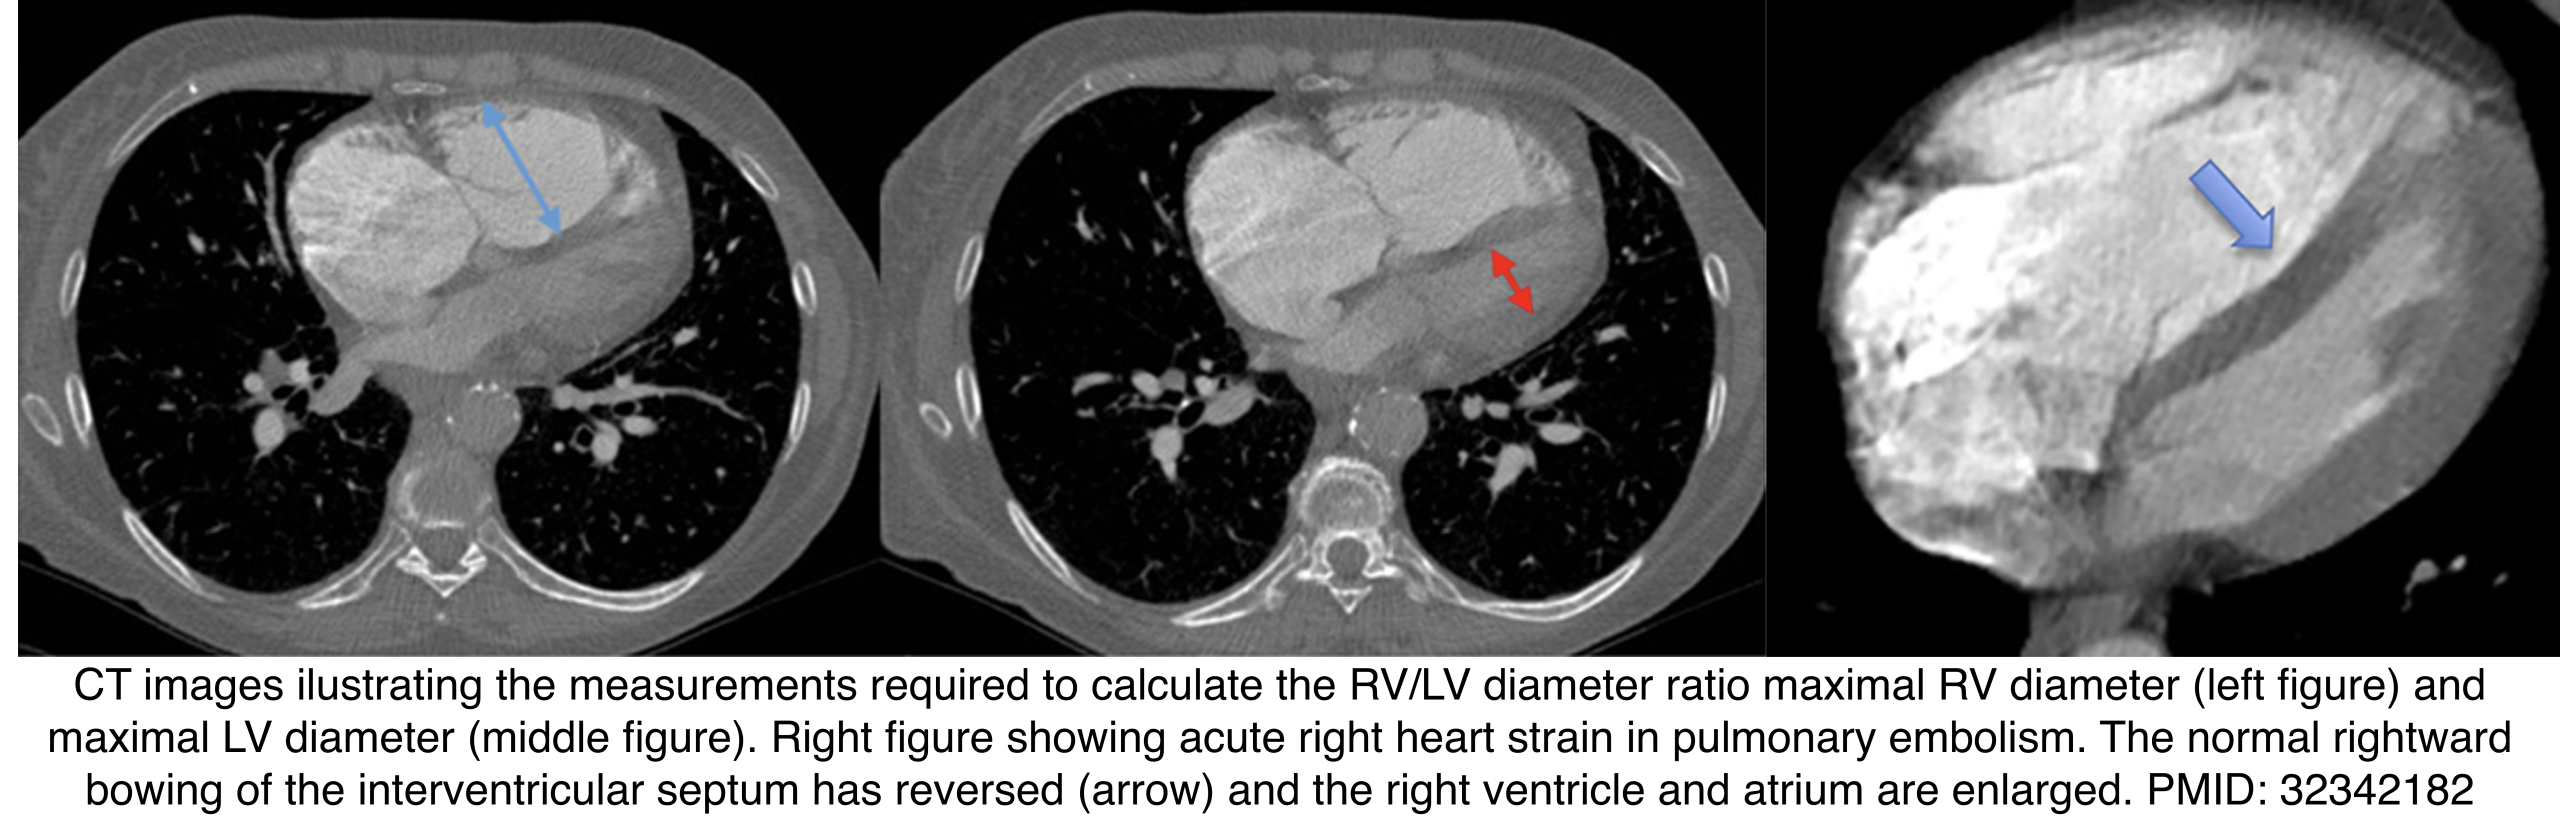

◾️RV dilation

- RV > LV ratio suggests RV dilation. Measure maximal diameters of both ventricles (may require multiple CT slices).

- Measured in a plane perpendicular to the septum.

- Limitation: Less reliable in patients with LV enlargement.

- ⎮Transverse diameter >57 mm in females or >60 mm in males

- Performance: ~65% sensitivity, ~92% specificity.

- Septal bowing: Leftward bowing of the interventricular septum can occur in acute PE or chronic pulmonary hypertension.